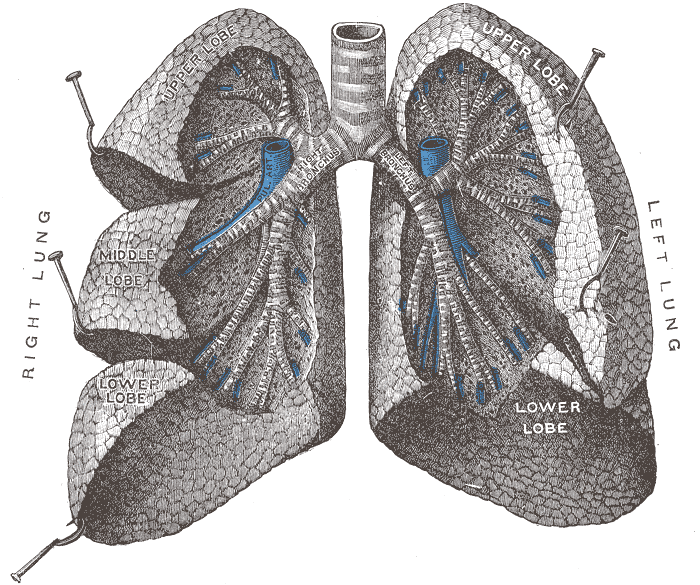

Good

illustration of the lobes of the lung, they removed the upper right (smallest)

lobe on me: